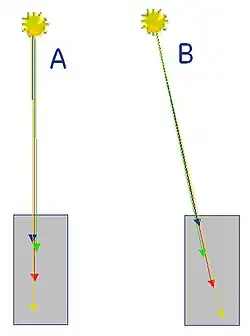

Erläuterung

Man stelle sich eine Nuklidanreicherung vor, die sich in der Nähe eines wassergefüllten Zylinders mit 30 cm Durchmesser befindet. Die dort zerfallenen Nuklide senden ihre Vernichtungsstrahlung in alle Raumrichtungen aus. Es sollen zwei Fälle betrachtet werden: Fall 1: Die beiden entstandenen Photonen 1 und 2 fliegen exakt tangential von der Objektoberfläche weg (violette Pfeile), weder Photon 1 noch Photon 2 durchdringt irgendeinen Teil des Zylinders. Fall 2: Photon 1 zielt radial in Richtung Zylindermitte. Naturgemäß entfernt sich Photon 2 vom Zylinder, ohne auch nur einen Teil des Zylinders zu durchdringen (nach oben weisender roter Pfeil). Die Wahrscheinlichkeit ist groß, dass Photon 1 beim Durchlauf von 30 cm Wasser absorbiert und damit Photon 2 zu einem „Single“ wird und damit für die Bildrekonstruktion nicht mehr zur Verfügung steht.

Würde die Absorption der Strahlung bei der Bildrekonstruktion unberücksichtigt gelassen, wären Artefakte die Folge; die gemessene Aktivitätsverteilung stimmte ohne Absorptionskorrektur nicht mit der tatsächlichen Verteilung überein.

Relevanz für die Quantifizierung von Anreicherungen

Die Wahrscheinlichkeit einer Absorption ist im Fall 2 (rote Pfeile) unabhängig davon, ob die Annihilation an der Oberfläche (Ort A) oder in der Mitte des Objektes (Ort B) stattfand. Bei Annihilation an der Oberfläche (Ort A) durchläuft Photon 1 den gesamten Zylinder, Photon 2 nur Luft, bei Annihilation in der Zylindermitte (Ort B) durchlaufen beide Photonen den halben Zylinder, was zur selben Absorptionswahrscheinlichkeit führt. Da die Absorptionswahrscheinlichkeit somit nur von der Gesamtschwächung des durchstrahlten Volumens, nicht jedoch vom Ort der Annihilation auf der Koinzidenzlinie abhängt, ermöglicht dies eine tiefenunabhängige Quantifizierung der Nuklidanreicherung.